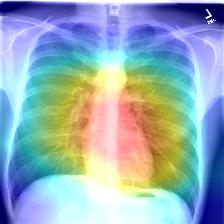

Implementation of Class Activation Maps to localize the disease visualizations on XRays. Specifically 3 different approaches and significance of each.